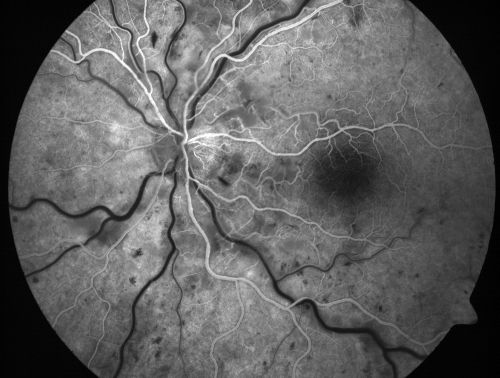

Non-Ischemic Central Retinal Vein Occlusion in Young Man (30 years) - Many Cotton Wool Spots

30-year-old man with a history of a central retinal vein occlusion for which he was first examined on 2 months ago and his vision then was 4/200.  He responded nicely to two Avastin treatments. OD is 20/20, OS is 20/60